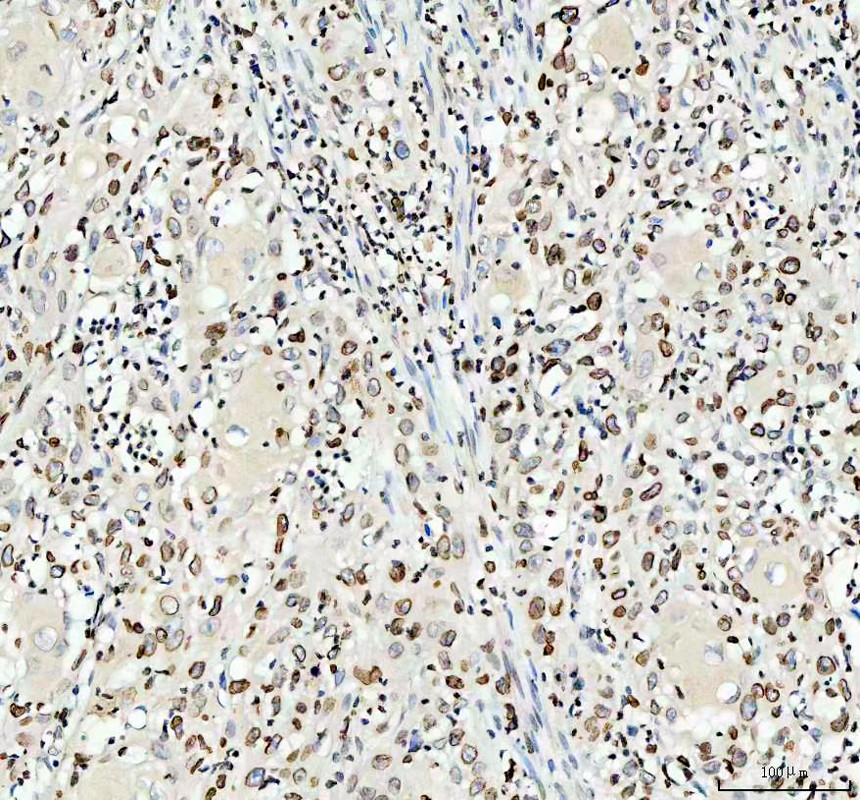

IHC analysis of Lamin B1/LMNB1 using anti-Lamin B1/LMNB1 antibody (PB9611).

Lamin B1/LMNB1 was detected in a paraffin-embedded section of human glioblastoma tissue. The tissue section was incubated with rabbit anti-Lamin B1/LMNB1 Antibody (PB9611) at a dilution of 1:200 and developed using HRP Conjugated Rabbit IgG Super Vision Assay Kit (Catalog # SV0002) with DAB (Catalog # AR1027) as the chromogen.